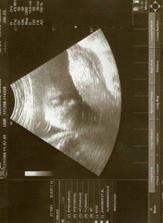

tak tohle album obsahuje vše co se týká našeho prvního miminka, které nosím pod svým srdíčkem, výbavičky co chystáme a co bychom chtěly nachystat.. Narodit se má 6.3.2009 , nevíme co to bude - asi necháme jako překvapení.